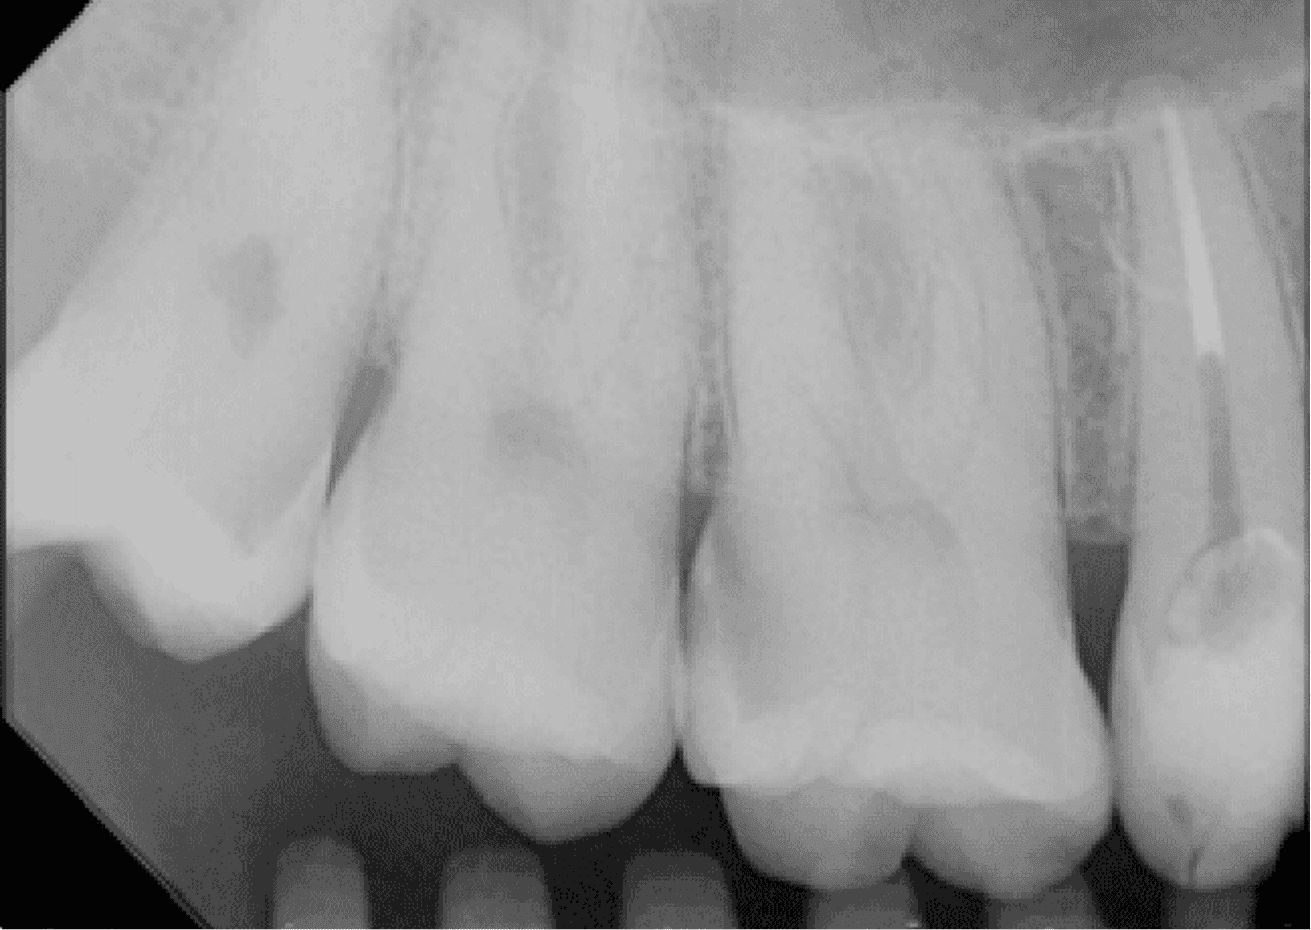

O exame clínico inicial, do dente 15, apresentava selamento provisório com ionômero de vidro e exame radiográfico apresentava alívio de 2/3 do conduto.

No planejamento reabilitador, foi reabilitado com dois pinos Whitepost SYSTEM cimentados com a combinação de sistema adesivo Ambar Universal APS e cimento resinoso dual Allcem CORE, que também foi utilizado para construção do núcleo de preenchimento.